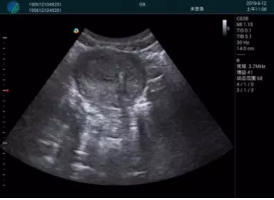

可視化甲狀腺穿刺引導(dǎo)

頸動脈血流充盈飽滿,無外溢

肝內(nèi)血管顯示清晰,血流敏感無外溢

病例二:

甲狀腺囊性結(jié)節(jié),囊壁鈣化,透聲好

甲狀腺囊性占位

2001年美國健康護理研究和質(zhì)量監(jiān)督局(AHRQ)批準了一項關(guān)于提高患者安全性的報告,建議:在頸內(nèi)靜脈中心置管術(shù)時使用超聲引導(dǎo)。此后超聲引導(dǎo)穿刺被用于幾乎所有的急診穿刺操作,尤其是血管穿刺。

便攜超聲在急診穿刺中的應(yīng)用:

* 提高了穿刺成功率

* 減少了穿刺損傷及并發(fā)癥

* 縮短了操作時間

* 減輕了患者痛苦